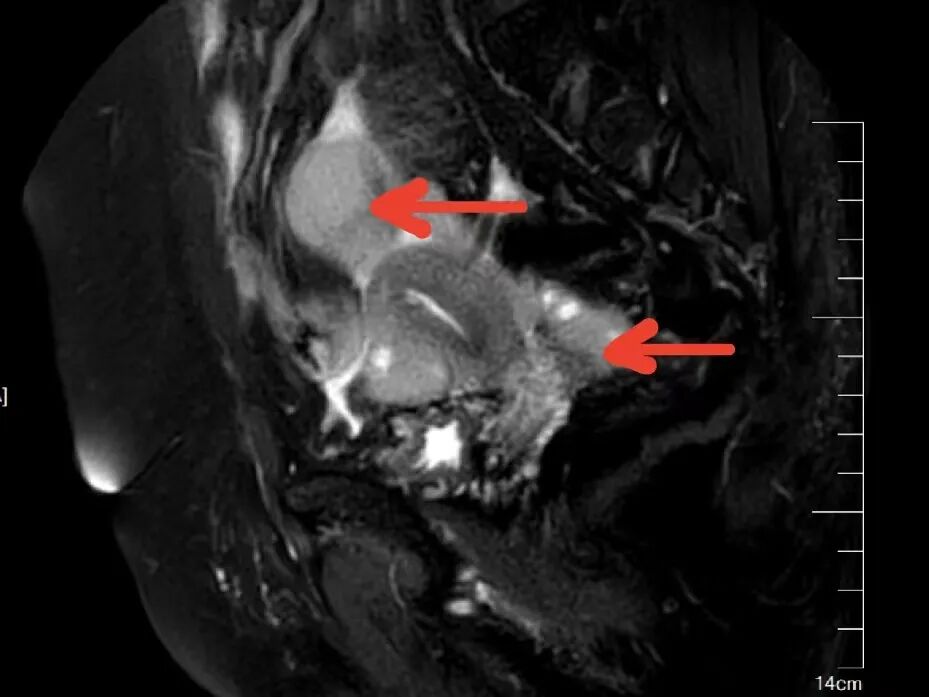

65岁的陈女士,因反复口干、多尿多饮、伴疲劳乏力,偶有胸闷,监测空腹指尖血糖超过11mmol/L,来我院内分泌科住院治疗,入院后完善相关检查,其中在子宫双附件彩超筛查中发现子宫上方见一类圆形低回声团,大小约37x32x37mm,边界不清,内部回声不均匀,这意味着不排除肿瘤可能。在积极控制血糖的同时,进一步完善了盆腔MR增强等针对性检查,结果提示:双侧附件区、

子宫直肠陷凹

及子宫周围多发结节状、团块状异常信号影,考虑附件区恶性肿瘤, 伴子宫直肠陷凹及子宫多发转移。内分泌科主任颜文盛考虑到该患者病情复杂,立即申请妇科会诊。经过妇科团队会诊,近期可能需要专科手术干预治疗,他与家属充分沟通后,家属果断选择转入广州市花都区人民医院妇科。

盆腔MR(红色箭头为病灶)

盆腔MR(红色箭头为转移病灶)